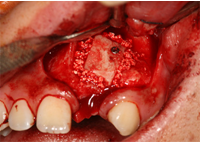

Cấy ghép Implant

![]() |

| Cấy ghép implant R24 |

Trong tất cả các ca implant răng cửa, bệnh nhân đều có răng tạm trong thời gian chờ phục hình chính thức trên Implant. Như vậy, các hoạt động giao tiếp xã hội của bạn đều diễn ra bình thường.